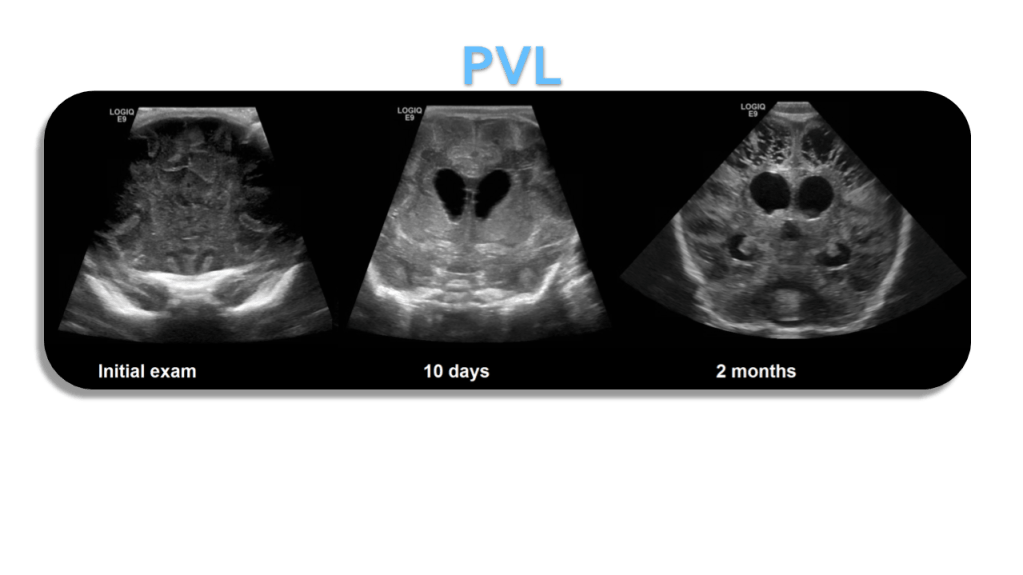

Periventricular Leukomalacia (PVL)

- Periventricular white matter normally hyperechoic but < choroid plexus

- Increased echogenicity around the ventricle (white matter ischemia)

- Progresses to cystic spaces that replace normal brain

- (white matter necrosis)

- Cystic changes typically appear 2-6 weeks after vascular insult

- Significant neuro-motor impairment follows

Periventricular leukomalacia (PVL), or white matter injury of prematurity affecting the periventricular zones, typically results in cavitation and periventricular cyst formation.

PVL is most common in premature neonates (less than 34 weeks gestational age with a median gestational age of 30 weeks) and <1500 grams at birth.

Cerebral palsy and intellectual disabilities are common sequela of PVL.

It is thought to occur as a result of hypoxic-ischemic lesions resulting from impaired perfusion at the watershed areas, which in premature infants are located in a periventricular location.

Early on the periventricular white matter may increase in echogenicity ultimately resulting in cyst formation.